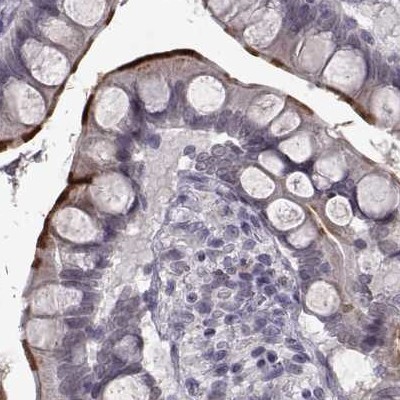

Immunohistochemistry analysis in human duodenum and liver tissues using Anti-SLC28A2 antibody. Corresponding SLC28A2 RNA-seq data are presented for the same tissues.